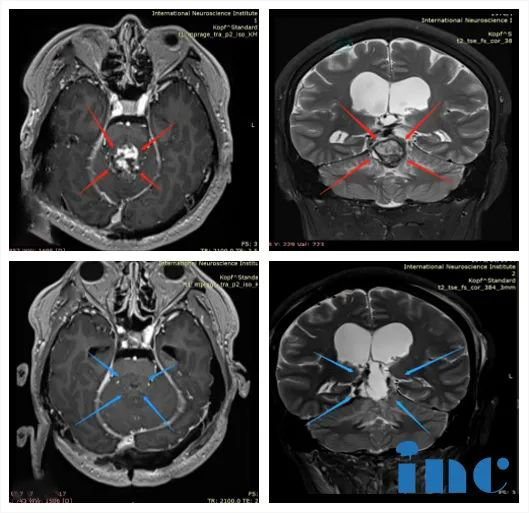

01、脑干海绵状血管瘤

简要病史

2岁多的伊伊因持续20多天的双眼斜视、不自主扭头、走路不稳就医,结果查出来病因是“脑干海绵状血管瘤破裂出血”。脑干出血本身就是危急重症,不及时手术生命堪忧。加上患儿年龄太小,病变又在脑干桥脑位置,手术难度和风险可以说是翻倍的。国内专家问遍了,没有医生可以为伊伊手术。

INC国际教授远程评估意见

找到INC德国专家Helmut Bertalanffy(巴特朗菲)教授后,一家人总算看到了生机。这位被国内患者尊称为“巴教授”的专家仔细评估伊伊的病历及影像资料后表示:“孩子具有明确的手术指征,对于这种脑干部位的海绵状血管畸形只有通过手术可以合适治疗,我的切除率将达到99%-全切。”

INC国际教授主刀手术后

伊伊的脑干海绵状血管瘤得到全切。术后二天出ICU,术前症状均好转。术后一周即出院,术后1.5月复查,斜视、走路不稳症状消失,面瘫减轻,行动能力完全正常,没出现任何新的并发症。如今,伊伊已回归了原有的活力,术后伊伊的生长发育、智力发育都完全恢复了正常,而且今后不会再受病魔威胁,他将和全部健康人一样有一个正常的人生。